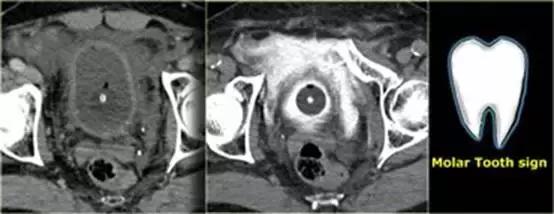

膀胱造影前后CT对比图像

膀胱中导尿管有对比剂, 膀胱直肠隐窝中也有渗出的对比剂。

‘磨牙征’ 提示腹膜外膀胱破裂。

补充知识:膀胱破裂示意图